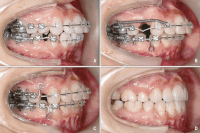

Việc niềng răng một hàm thường được áp dụng cho các vấn đề cụ thể, chẳng hạn như sự lệch lạc của hàm trên hoặc hàm dưới, hoặc sự không đều của răng trên một hàm. Trong những trường hợp này, niềng răng một hàm có thể đạt được kết quả điều trị tốt mà không cần phải niềng toàn bộ hàm. Điều này cho phép bác sĩ nha khoa tập trung vào việc giải quyết vấn đề cụ thể và đạt được kết quả điều trị hiệu quả hơn.

Khi niềng răng một hàm, việc theo dõi tiến trình điều trị thường đơn giản hơn. Bác sĩ nha khoa có thể dễ dàng quan sát và điều chỉnh tình trạng răng miệng của bệnh nhân mà không cần phải quản lý cả hai hàm. Điều này giúp cải thiện khả năng điều chỉnh và đảm bảo rằng quá trình điều trị diễn ra suôn sẻ và hiệu quả.